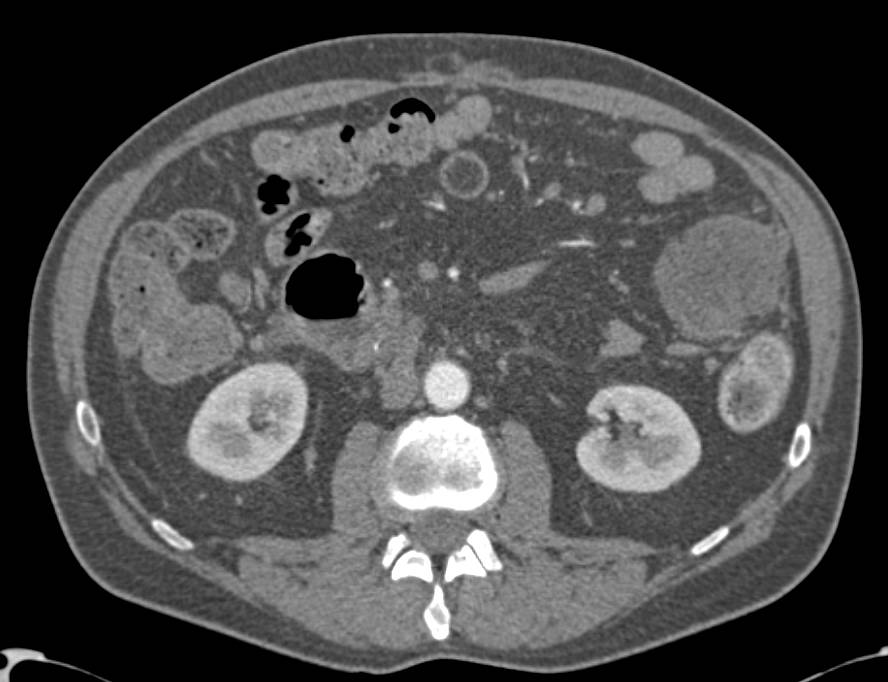

Pancreatic Cancer Invades the Duodenum. Stents Placed in the Duodenum